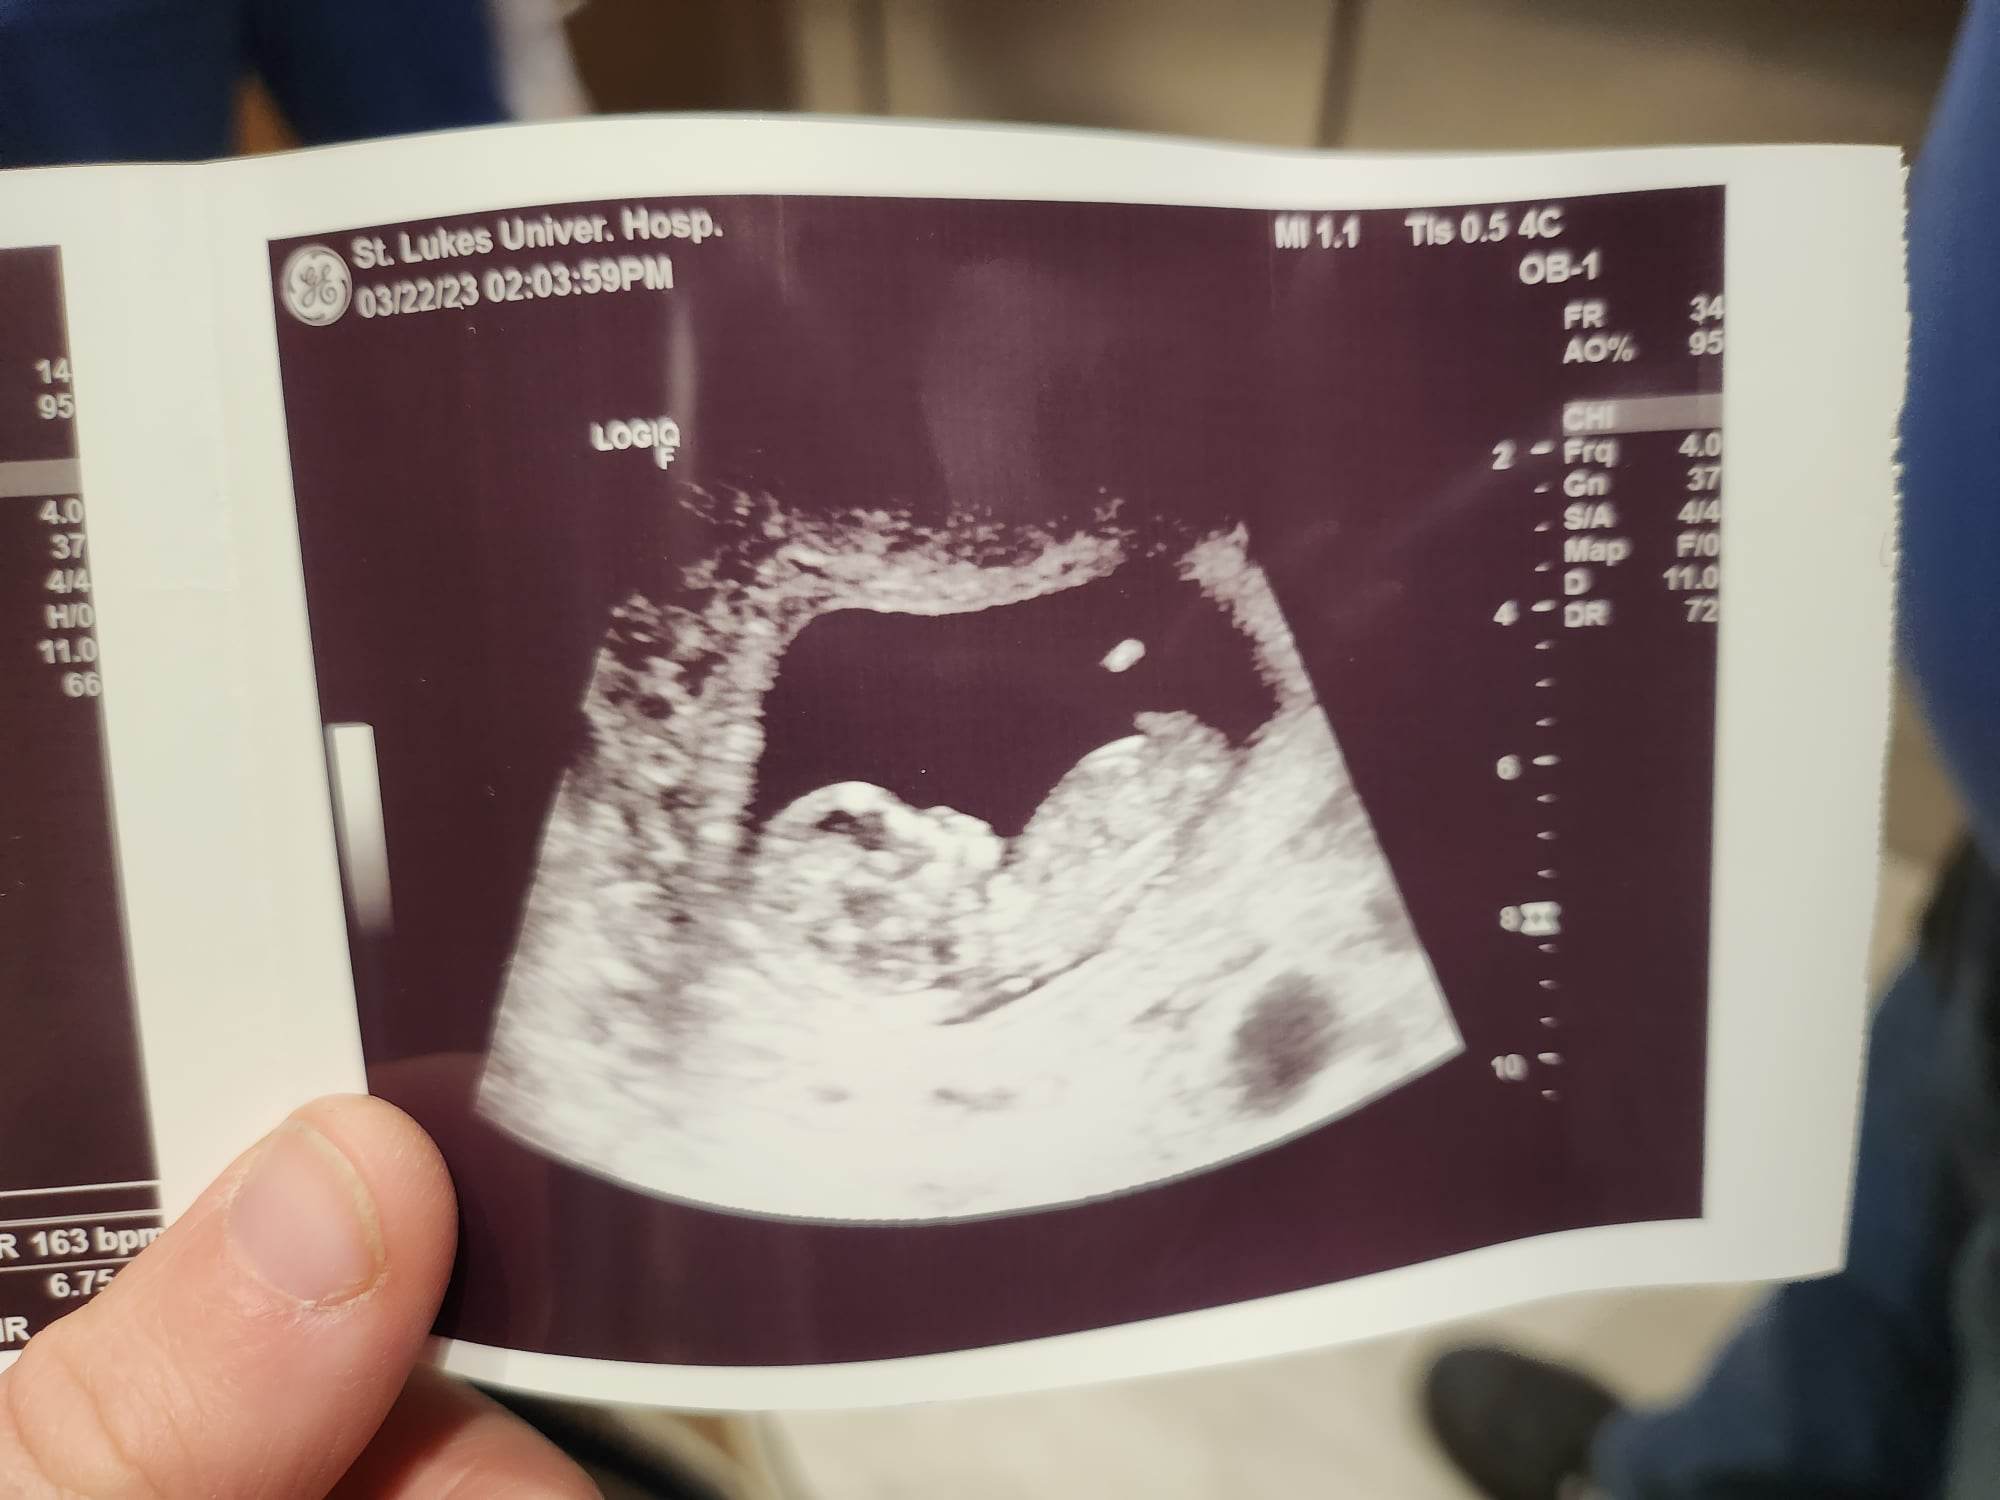

Our story is a very long one, filled with misdiagnosis and medical malpractice. I am going to skip all of that because I don't feel like crying today. In 2020 my husband and I, after 14 years of marriage and many unsuccessful attempts to have a child found the Mosie kits. We also were unsuccessful with them. After months of that we went and reached out to a fertility clinic and found out that the reason for all of my problems was a microperforated hymen that had been misdiagnosed as "pelvic pain disorders" and "anxiety" since I was young. In 2021 my husband almost died from Covid; the virus attacked his heart and lungs and he had heart surgery in January 2022 to save his life. In July 2022, I had my surgery to correct the microperforated hymen and the rest of the problems that had been ignored because my husband is on very heavy cardiac medication we decided to give the Mosie Baby Kit a one final try. We were released to try again in December 2022. We tested positive on our first month of trying in January 2023. Thank you Mosie Baby!